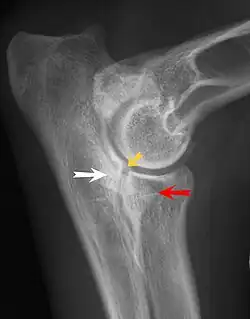

Fragmentierung des Processus coronoideus medialis ulnae (FCP)

* gelber Pfeil: Stufe zwischen den gelenkbildenden Anteilen von Elle und Speiche

* roter Pfeil: fehlende vordere Kontur des Processus coronoideus (hinweisend auf einen FCP)

* weißer Pfeil: Sklerosierung der Ulna (typisch für eine Osteoarthrose).

Bei der klinischen Untersuchung zeigt sich eine Schmerzhaftigkeit bei starker Streckung oder Beugung des Gelenks. Im Röntgenbild sind vor allem die Verschattungen im Bereich der Elle, der Verlust der Knochenbälkchenzeichnung, eine undeutliche vordere Kontur im latero-lateralen Strahlengang (seitliche Projektion) und gegebenenfalls die Frakturlinie des Fortsatzes sichtbar. Ein vollständiger Abriss des Processus coronoideus ist jedoch selten.[10] Aufgrund der mangelnden Kongruenz können sich eine Stufe zwischen Speiche und Elle und ein ungleichmäßig breiter Gelenkspalt darstellen. Diese Inkongruenz tritt bei 60 % der Patienten mit einem FCP auf und lässt sich mittels eines Quotienten darstellen. Hierzu werden die Länge der Incisura trochlearis sowie die Entfernung zwischen der Spitze des Processus anconaeus und der Spitze des Processus coronoideus lateralis ulnae gemessen und durch einander geteilt. Liegt der Quotient beider Werte über 1,15, gilt das Ellenbogengelenk als inkongruent.[5] Die mit dem FCP verbundene Arthrose zeigt sich bei schwereren Formen in Lippenbildungen der angrenzenden Knochenkonturen. Knochenanbauten treten vor allem am innen liegenden (medialen) Rand der Elle und des Oberarmknochens auf. Eine sichere Diagnose eines FCP ist am Röntgenbild nur selten möglich.[13] Eine Computertomografie und Arthroskopie kann die Diagnose FCP untermauern.